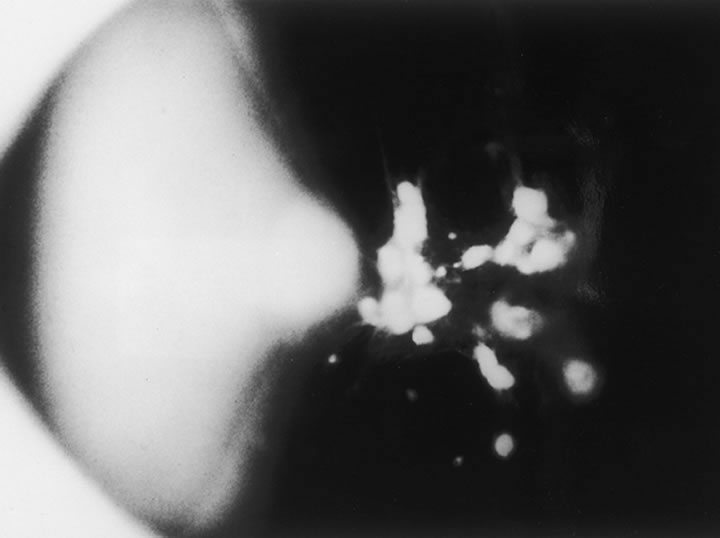

There is a mechanism for the elimination of foreign and degenerated substances from the vitreous that is found partly in the region of the optic disc. When India ink is injected into the anterior portion of the vitreous in a rabbit eye and the enucleated eye examined at varying intervals, it is noted the ink particles are eliminated from the vitreous by way of the optic nerve.25 Later the particles are removed by phagocytic cells that appear to enter the vitreous body from the region of the optic nerve and ciliary body. Surgical treatment may also affect the cellular composition of the vitreous. Cryopexy induces a macrophage influx into the vitreous cavity.26 This may play a role in the clearing of vitreous opacities.